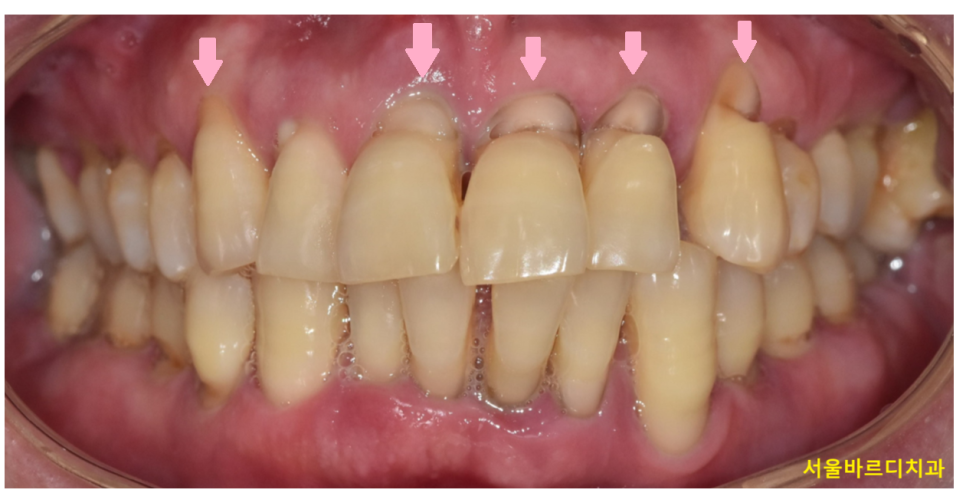

사진을 한번 봐볼까요~?

치아가 잇몸쪽 부위가 파여있죠~?

이런 증상을 우리는 치경부마모증이라고 부릅니다.

230525 심하게 파인 치아

문제는 진행이 된다는 것입니다.

그대로 두게되면 더 깊이 파이면서

치아 내부 신경이 드러날 수 있습니다.

진행이 계속되면 치아가 똑! 부러질 수도 있고요.